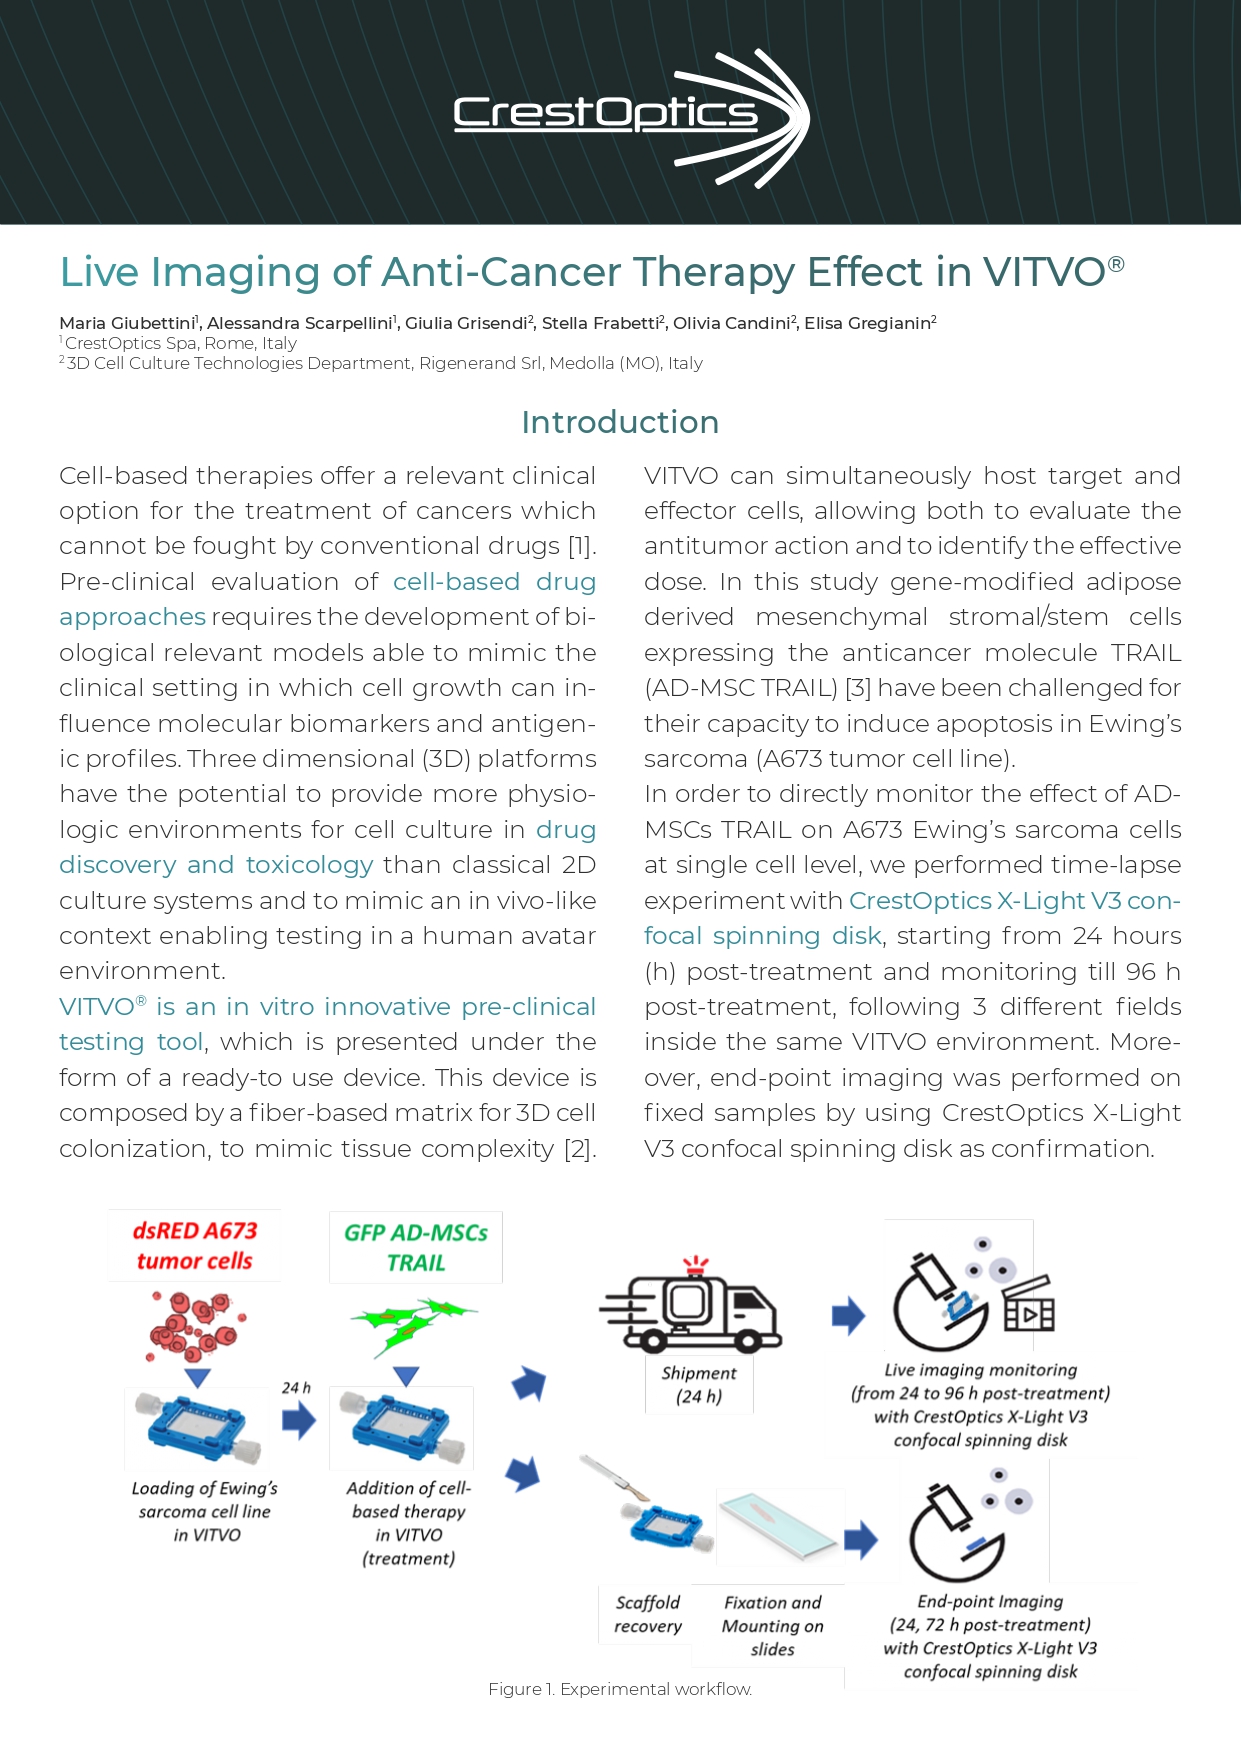

VITVO® is an in vitro innovative pre-clinical testing tool, which is presented under the form of a ready-to-use device. This device is composed by a fiber-based matrix for 3D cell colonization, to mimic tissue complexity [2]. VITVO can simultaneously host target and effector cells, allowing both to evaluate the antitumor action and to identify the effective dose. In this study gene-modified adipose derived mesenchymal stromal/stem cells expressing the anticancer molecule TRAIL (AD-MSC TRAIL) [3] have been challenged for their capacity to induce apoptosis in Ewing’s sarcoma (A673 tumor cell line).

In order to directly monitor the anti-cancer therapy effect of AD-MSCs TRAIL on A673 Ewing’s sarcoma cells at single cell level, we performed time-lapse experiment with CrestOptics X-Light V3 confocal spinning disk, starting from 24 hours (h) post-treatment and monitoring till 96 h post-treatment, following 3 different fields inside the same VITVO environment. Moreover, end-point imaging was performed on fixed samples by using CrestOptics X-Light V3 confocal spinning disk as confirmation.

Figure 1. Experimental workflow.

VITVO loading: VITVO bioreactors (Rigenerand srl, Medolla, MO, Italy) were first primed with 1.4 ml of media alone by using a 2.5 ml syringe (Becton Dickinson and Co, Franklin Lakes, NJ, USA) to ensure a complete wetting of 3D matrix. Next, the A673 target cells (500.000/VITVO) were resuspended in 1 ml of culture medium and seeded in VITVO, and after 24 h the effector AD-MSC TRAIL (50.000/VITVO) was added in VITVO following the loading procedure already used for A673 cell line.

Co-culture of effector: target (1:10) was maintained in culture till 96 h.

Microscope monitoring and 3D imaging: Time lapse acquisitions have been performed with a Nikon Ti2 Eclipsed equipped with CrestOptics X-Light V3 confocal spinning disk, Okolab incubator at 37°C (H301-K-FRAME, kindly provided by Okolab), Celesta laser source (lambda used 470 and 545; Lumencor) and Prime 95B camera (11 um pixel size, 1608×1608 pixels, Photometrics). For 72 h long-term live imaging, Nikon 4x Plan Apo objective (air, 0.2 NA) has been used with a Z step of 10 um for a total Z volume of 500 um. Three different areas in the VITVO device have been monitored with acquisition rate of 30 min for the first 6 h, then every hour for the rest of the video. Imaging of living cells at the end of the video has been performed with a 4x Plan Apo (air, 0.2 NA) with a Z step of 10 um for a total Z volume of 450 um.

Acquisitions of fixed samples, collected at specific time points (24 h and 72 h post treatment), have been performed with CrestOptics X-Light V3 confocal spinning disk by using a 10x Plan Apo (air, 0.45 NA) objective with a Z step of 2 um for a total Z volume of 100-150 um.